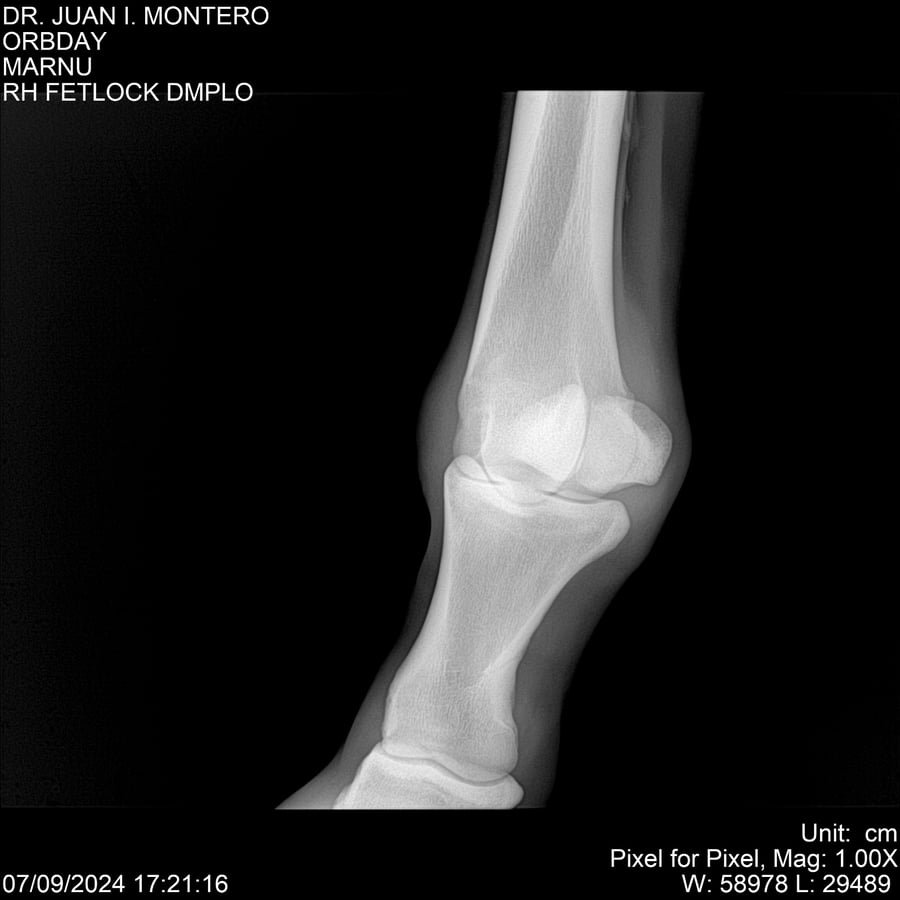

• Empresa: Abelenda N. R., Walter Hugo